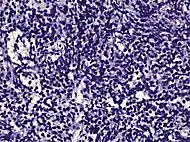

Acinar adenocarcinoma - 93%[2] | Adenocarcinoma (not otherwise specified/ conventional/ usual acinar)[3] |

77%[notes 2] | 54%[notes 2] | ![]() |

Acinar adenocarcinoma

These constitute 93% of prostate cancers.[2]